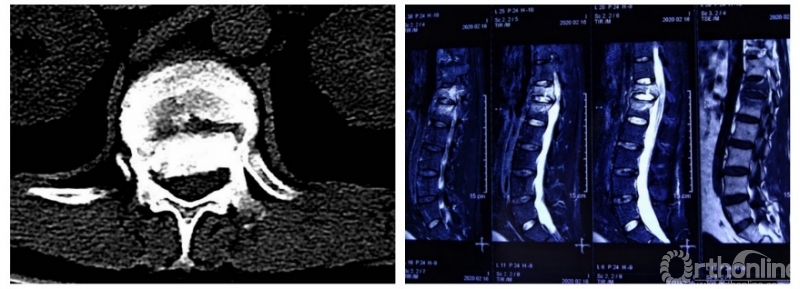

术后脊柱固定情况

不到2小时,手术完成了,患者被送ICU复苏观察。

2月23日,患者从ICU转入普通病房,其生命体征平稳,双下肢疼痛过敏症状明显好转,双下肢感觉功能基本恢复,双踝肌力4级,手术疗效理想。